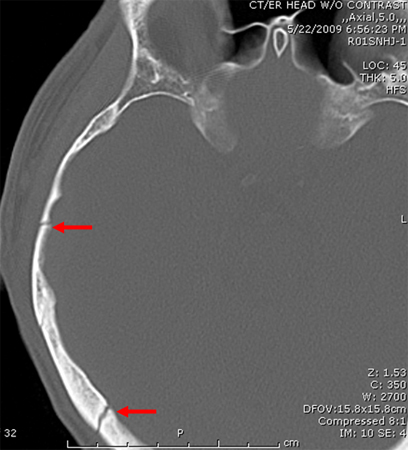

Fratura parietal linear sem depressão

Do acervo de aulas de Demetrios Demetriades, Division of Trauma and Surgical Intensive Care, LAC/USC Trauma Center, Keck School of Medicine da USC; usada com permissão